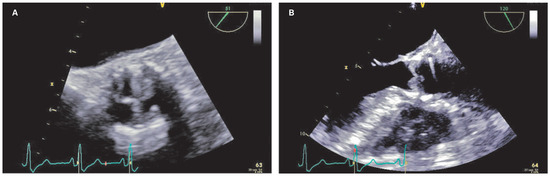

Late Transcatheter Aortic Valve Thrombotic Obstruction

by Simon Andreas Müggler, Sabrina Gisler-Jantzen, Jörg Gasser and David Tüller

Cardiovasc. Med. 2015, 18(7-8), 222; https://doi.org/10.4414/cvm.2015.00347 - 12 Aug 2015

Viewed by 144

Abstract

Late valve thrombosis is uncommon after transcatheter aortic valve implantation. Herein, we describe such a complication after transcatheter aortic valve implantation of an Edwards SAPIEN XT aortic bioprosthesis valve. Full article

Show Figures

Figure 1